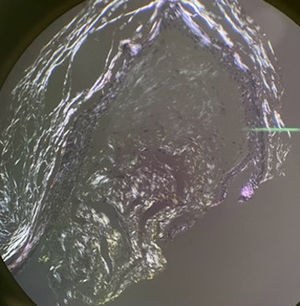

HistopathologyHistologic examination of one lesion revealed the presence of deposits of eosinophilic, amorphous, homogeneous material within the papillary and superficial reticular dermis (Fig. 2). Deposits tested positive with Congo Red staining and exhibited an apple-green birefringence under polarized light (Fig. 3).

Definitive diagnosis requires histologic confirmation, characterized by homogeneous hyaline deposits in the dermal papillae that show Congo Red and crystal violet positivity, and apple-green birefringence under polarized light.